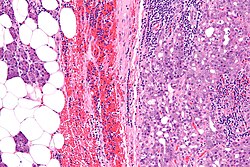

Normal salivary glands

Identifying the glands

The three main glands:

- Parotid:

- Serous glands - lower viscosity, acini (lobules).[2]

- Submandibular:

- Serous and mucinous glands.

- Serous ~90% of gland.

- Mucinous ~10% of gland.

- Serous demilunes = mucinous gland with "cap" consisting of a serous glandular component.

- Demilune = crescent.[3]

- Image: Serous demilunes (duke.edu).[4]

- Sublingual:

- Mucinous glands.

- Adipose tissue is found between the glands.

- It increases with age.